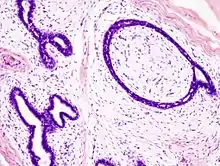

Microscopic

Fibroadenoma of the breast is a benign tumor composed of a biplastic proliferation of both stromal and epithelial components.[14][15] This biplasia can be arranged in two growth patterns: pericanalicular (stromal proliferation around epithelial structures) and intracanalicular (stromal proliferation compressing the epithelial structures into slit-like spaces).

These tumors characteristically display hypovascular stroma compared to malignant neoplasms.[16][17][11] Furthermore, the epithelial proliferation appears in a single terminal ductal unit and describes duct-like spaces surrounded by a fibroblastic stroma. The basement membrane is intact.[18]